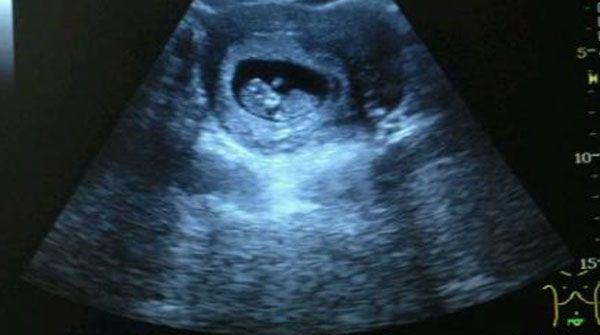

对于孕妈们来说,出现nt值结果为3.5mm时无疑是一个重大的打击,因为按照nt值正常范围标准来看,3.5mm已经相对于临界值已经高出了整整1mm,虽然情况很严重,但是此时最应该做的是要进行下一步的检查,即使是确诊患病,也能使得对女性的伤害程度降到最低。

nt值偏高的检查报告

nt值为3.5mm时胎儿的情况

从普遍医学认知的角度分析,3.5mm已经超出nt值的正常范围很多了,此时胎儿存在畸形的概率也大大提高,而且这种畸形往往是难以治愈的,如唐氏综合征、21-三体综合症等等,不仅对于孩子来讲是一种折磨,而父母也同样承担着心理压力。